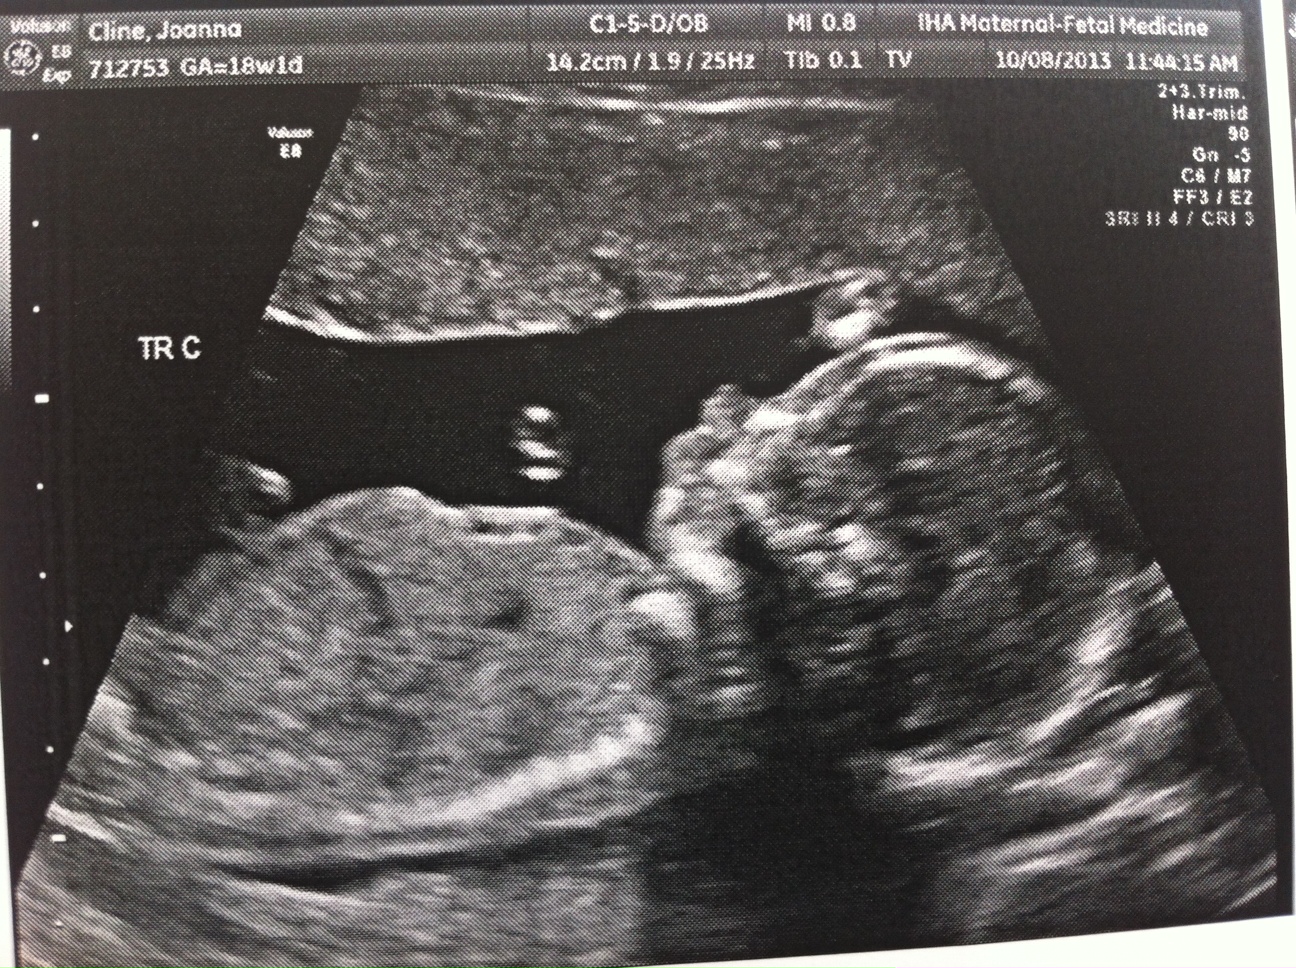

Everything still looks great. The triplets are growing but we won’t have another growth scan until my 22wk appointment. Heart beats look good and it’s clear they’re getting bigger (Today’s pictures attached.)